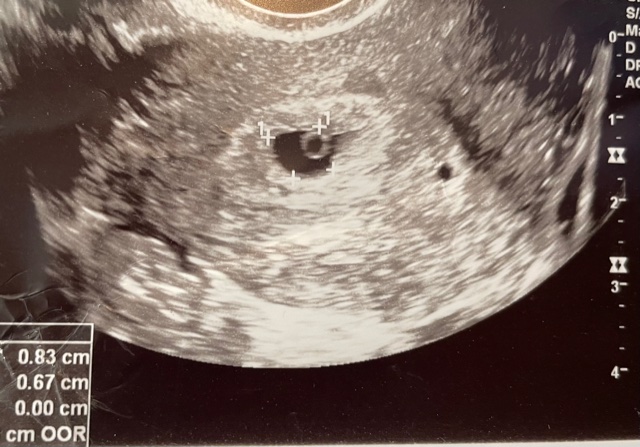

I went straight to the doctor to get my levels checked and to get an early ultrasound. And though I’d prepared for the worst, a little yolk sac that looked like a tiny ballon was visible on the screen. A baby was growing in there, and I had visual proof. At that point, I told my family and some close friends. I was performing in a musical at the time as well, so I told the director and the stage manager so they would know what was going on with me, both physically and mentally.

As I surpassed 9 weeks, I was still sipping on seltzers with lime to avoid being found out, but I did loosen up a bit and told a few more friends. I knew that with each passing week, and with the vision of that ultrasound in my mind, I was closer to being “in the clear.” But then I had an ultrasound that week, and it looked exactly the same as it had in week 6. And the nurse couldn’t detect a fetal heartbeat. I was told that the doctor would call me back within the next couple of days to confirm, but it looked as though I had suffered from a missed miscarriage. Essentially, my baby had stopped growing right around week 6 or 7, but my body hadn’t registered the loss. My body had kept trucking right along as though the fetus was growing normally.